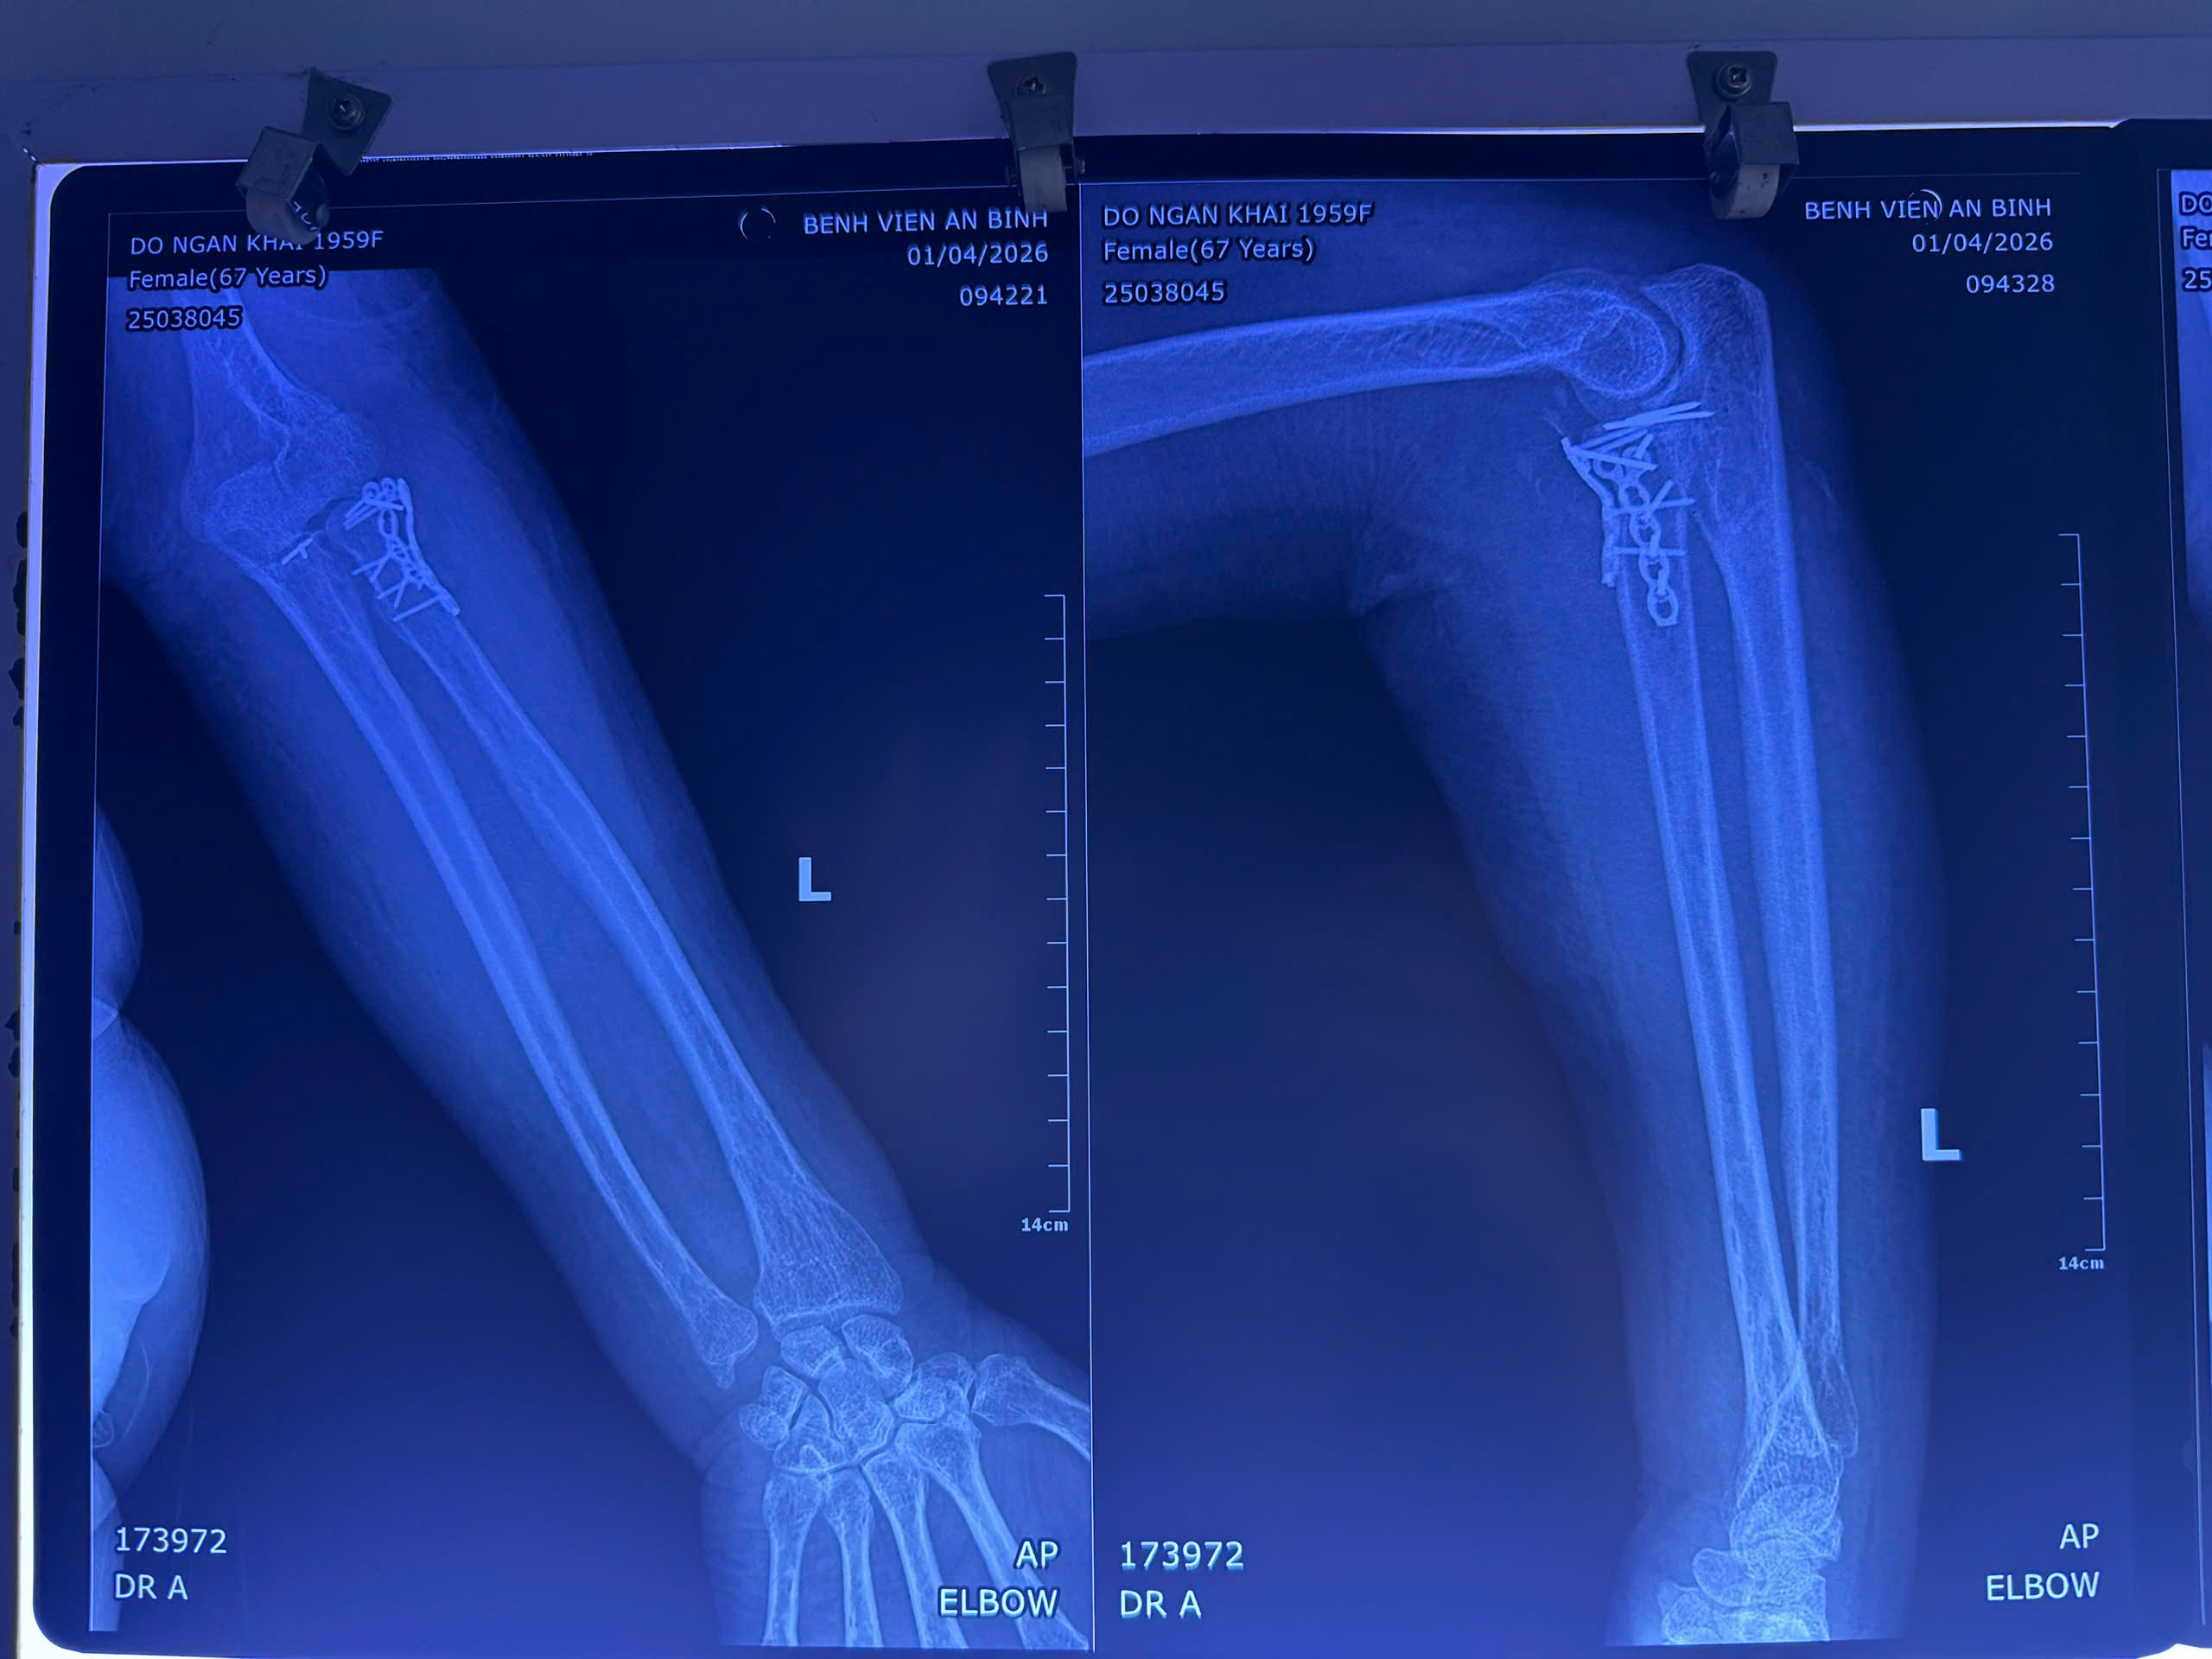

Bệnh nhân được xử trí kết hợp xương quay bằng nẹp vít, kết hợp xương mỏm vẹt xương trụ bằng kim Kirschner, khâu đính lại điểm bám dây chằng bên ngoài.

Hình chụp phim bệnh nhân bị gãy xương phức tạp kèm trật khớp. Ảnh: BVCC

Trường hợp thứ 2, bệnh nhân bị gãy hở độ II nhiều mảnh liên lồi cầu xương cánh tay kèm gãy 1/3 dưới, trật khớp quay trụ dưới cùng bên trái, tăng huyết áp, đái tháo đường.

Bệnh nhân được xử trí thành hai thì. Thì 1 là mổ cấp cứu cắt lọc, cố định bằng nẹp bột tránh nguy cơ nhiễm trùng; thì 2 là điều trị thực thụ như kết hợp liên lồi cầu xương cánh tay bằng nẹp vít, kết hợp xương quay bằng nẹp vít, cố định khớp quay trụ dưới bằng kim Kirschner.